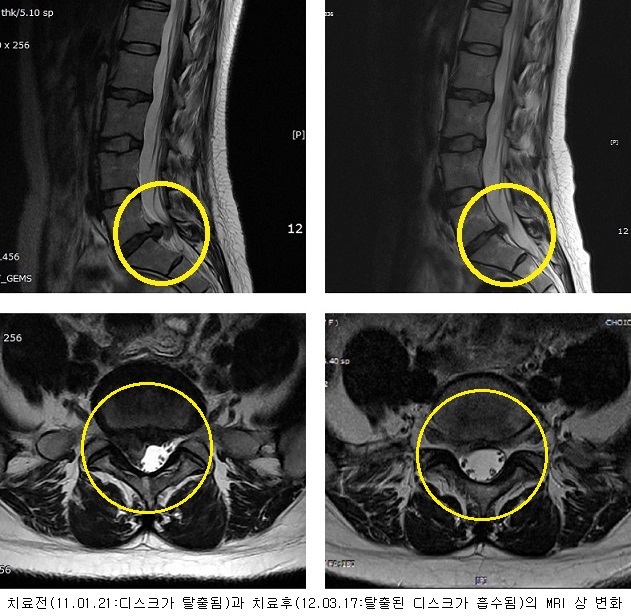

치료전후 MRI 비교

[허리디스크] 오OO (1981 년생)

2012-03-17